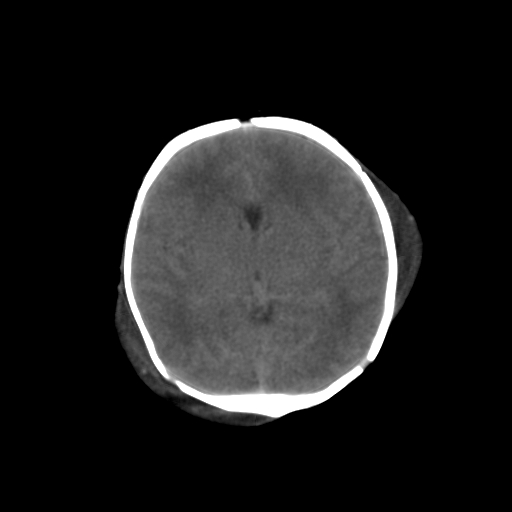

男,3天,患儿为剖腹产,生后嗜睡、拒乳。

1)考虑hie。2)sah?。3)右侧颞顶枕部及左侧颞顶部头皮血肿。

1、右侧颞顶枕部及左侧颞顶部头皮血肿。2、第五第六脑室。3、新生儿,脑白质密度还算可以,也无蛛血,不考虑hie。

脑室系统及脑沟裂闭塞,弥漫性脑密度减低,支持考虑hie,建议复查。右侧颞顶枕部及左侧颞顶部头皮血肿,另不除外胼胝体发育不良,复查